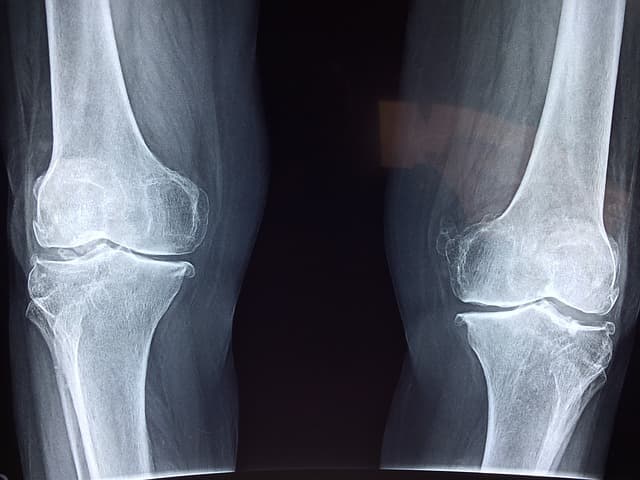

무릎 관절 스트레칭

- 한쪽 다리를 뻗고 발끝을 몸 쪽으로 당기면서 허벅지 뒤쪽을 늘려줍니다.

- 15초간 유지 후 반대쪽도 동일하게 진행합니다.

무릎 강화 운동 (벽에 기대어 앉기)

- 벽에 등을 대고 천천히 앉는 자세를 취한 후 5~10초 유지합니다.

- 하루 10회 반복하여 무릎 주변 근육을 강화합니다.